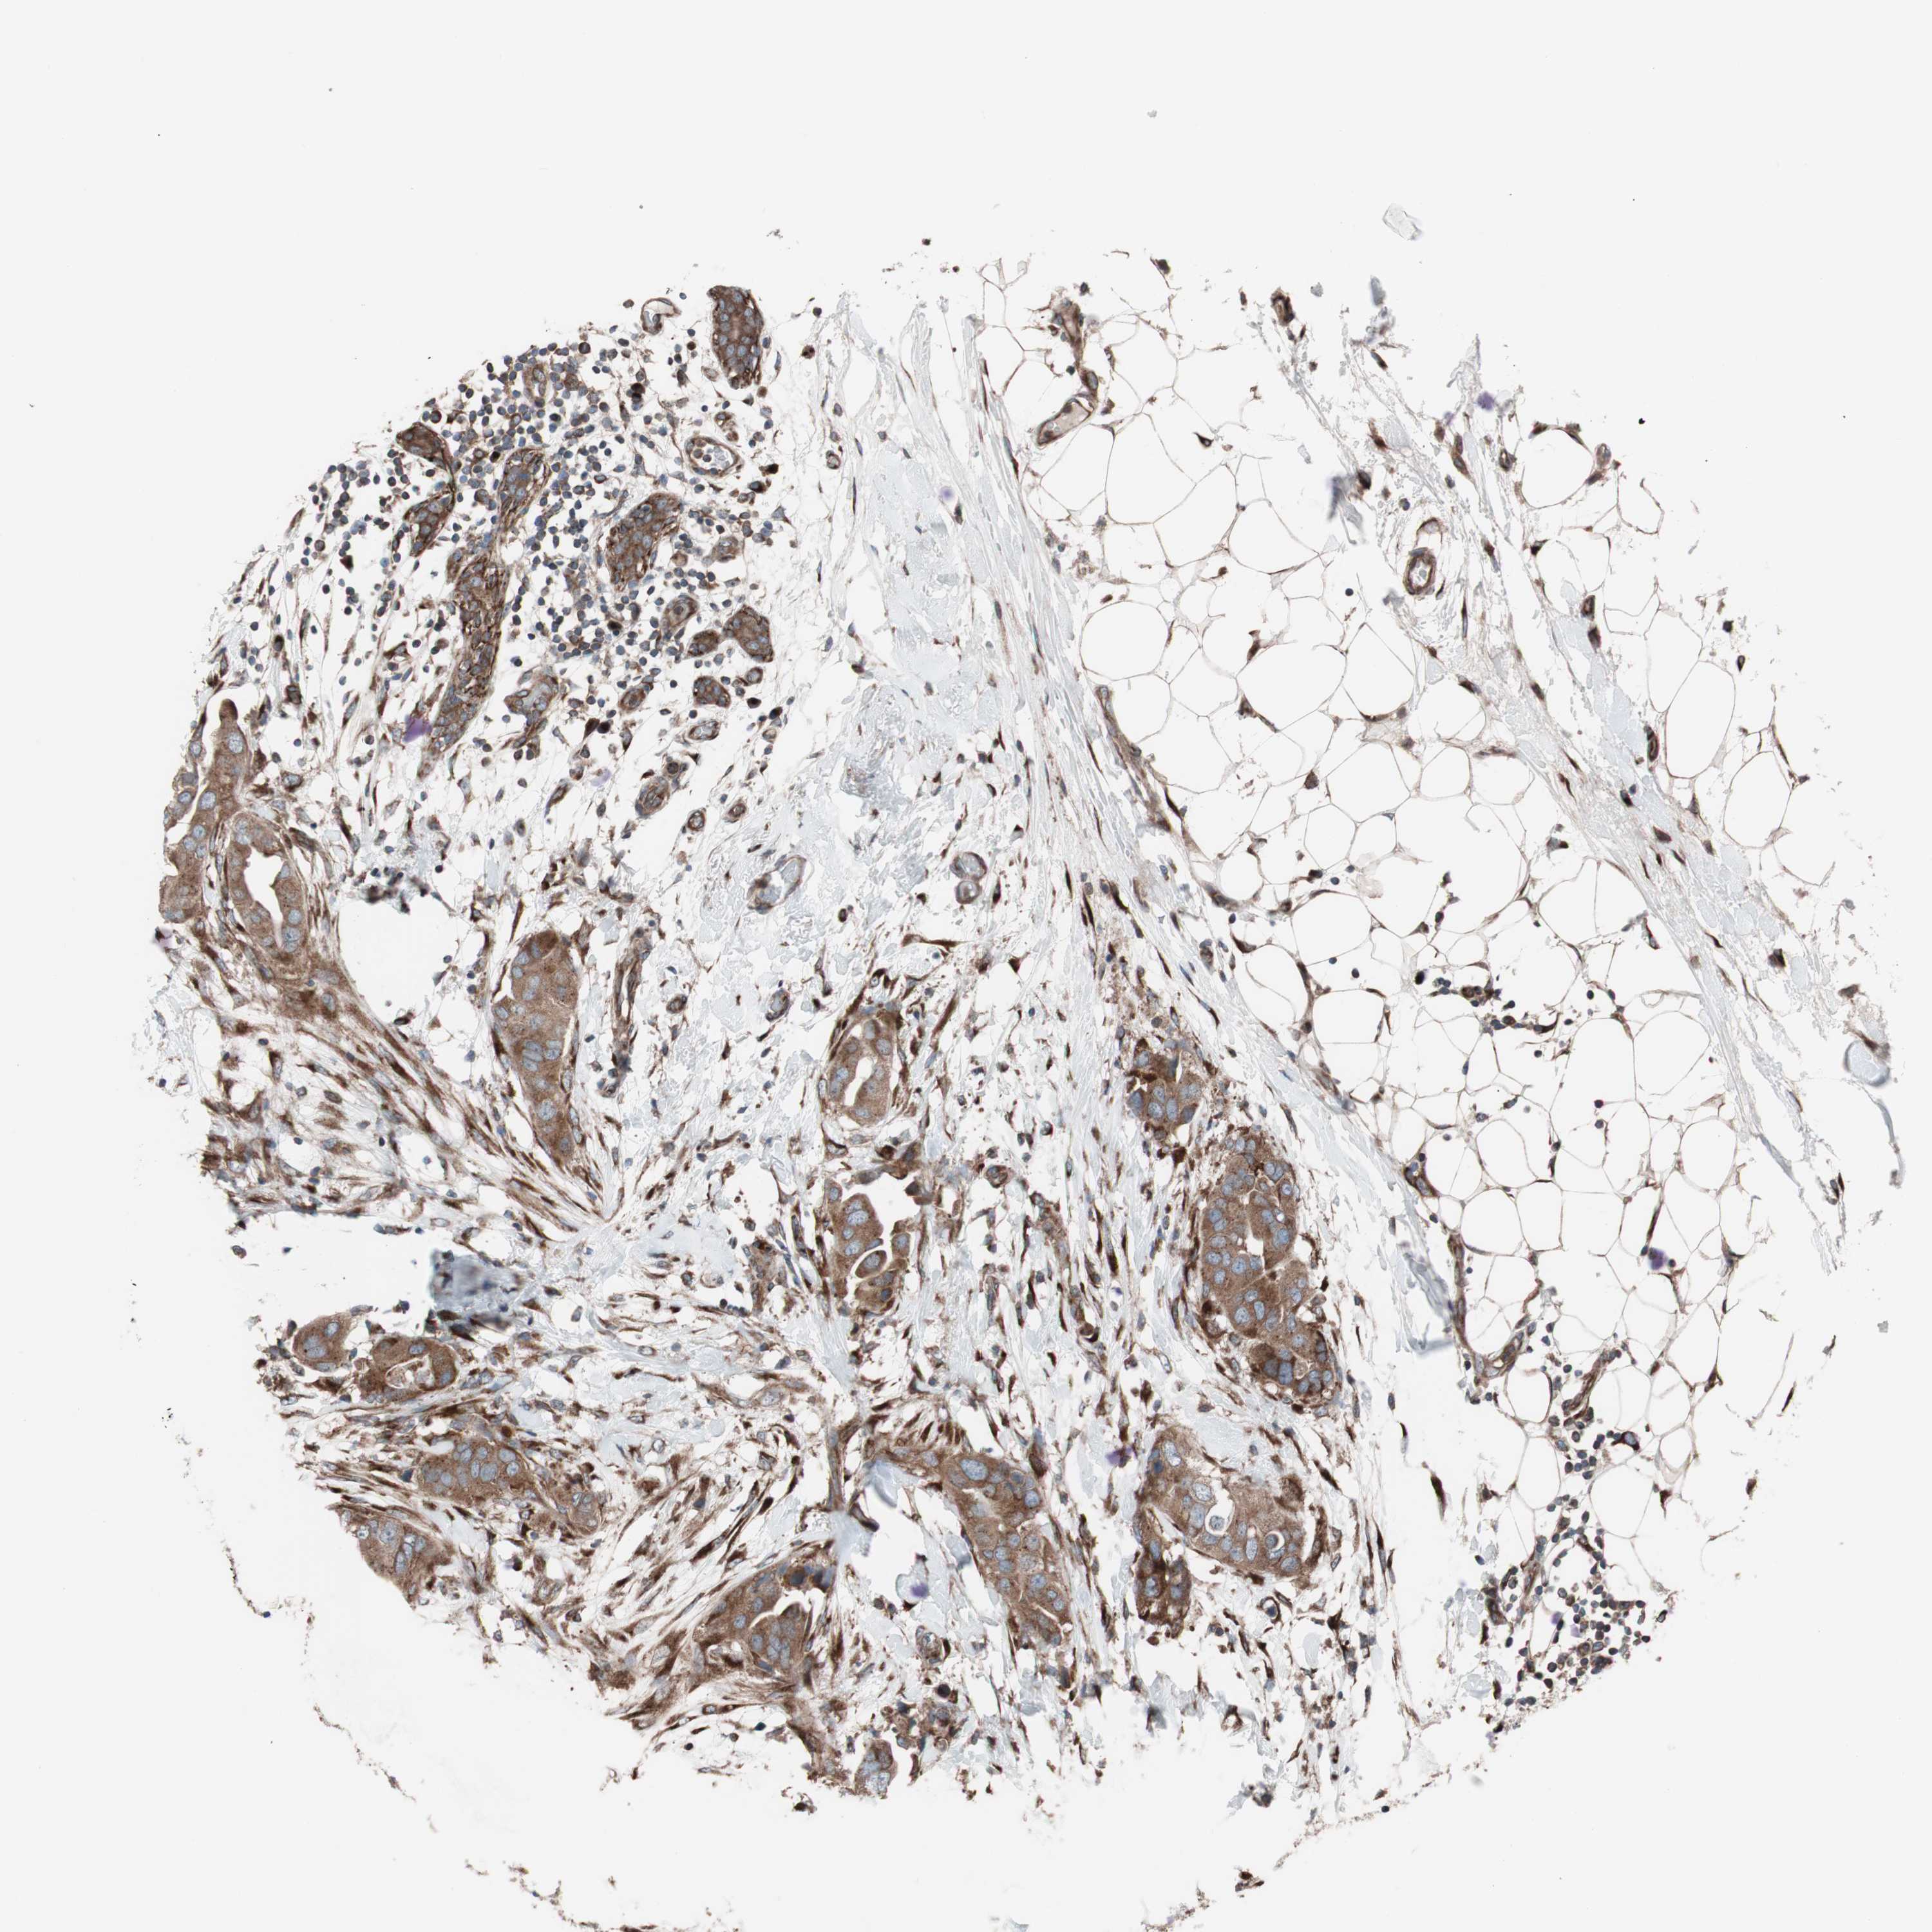

CANCER BREAST CANCER Show tissue menu

BRCA TCGA BRCA VALIDATION PROTEIN EXPRESSION

Breast cancer

Human cancer

Breast invasive carcinoma